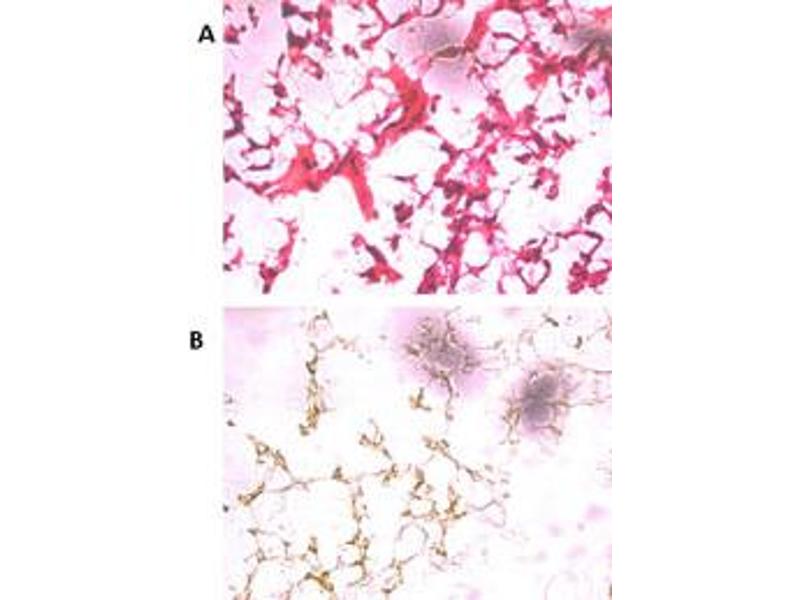

Western Blotting (WB), Enzyme Immunoassay (EIA), Immunohistochemistry (Paraffin-embedded Sections) (IHC (p))

This antibody is specific to UCHL5 (N-term).

This antibody is generated from rabbits immunized with a KLH conjugated synthetic peptide selected from the N-terminal region of human UCHL5.

ELISA: 1/1,000. Western Blot: 1/100-1/500. Immunohistochemistry: 1/50-1/100.